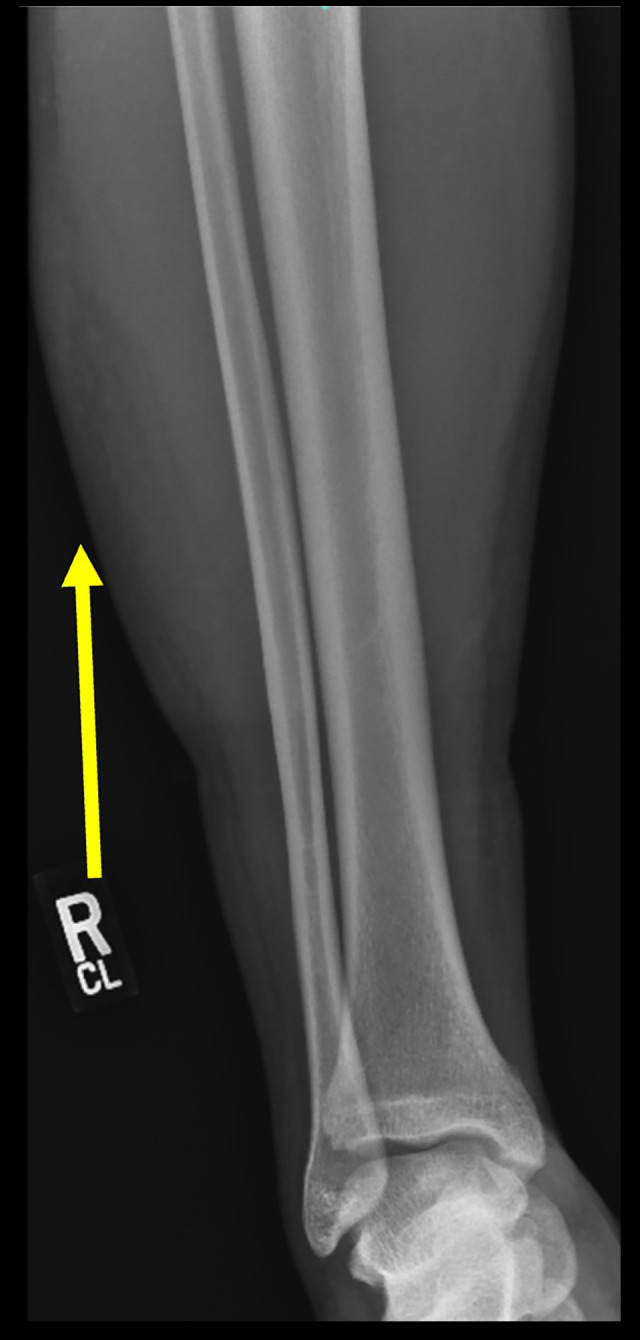

Morel-Lavallee病变(mls)是一种罕见的由高能外伤引起的闭合性软组织脱手套损伤,由于其罕见性和延迟表现而经常被遗漏,导致严重的并发症。在儿童和青少年患者中,mls尤其被遗漏和少报。我们描述了发生在小腿非典型病变部位的青少年MLL病例,以提高对该患者组的诊断和相关表现的认识,这可能不同于成人的表现,并导致诊断的不确定性,从而影响临床决策。病例报告一名18岁男性,在打篮球时滑到墙上,右外侧小腿出现疼痛和日益加重的肿胀。磁共振成像(MRI)显示液体收集最初怀疑是血肿。保守治疗失败后,多学科合作方法确认了MLL诊断,并通过超声引导下的抽吸引流病变。虽然患者已恢复所有正常的身体活动,但仍需对残余的肿胀和畸形进行监测。结论:我们的病例强调了诊断和治疗的挑战与非典型临床表现的MLL的青少年患者与运动损伤的小腿,突出的作用,影像学和多学科咨询在及时干预。与现有有限的mls文献一致,早期微创超声引导下的抽吸可能有利于指导后续治疗,但需要通过建立标准化的儿童和青少年管理指南来进一步研究和达成共识,以实现这一弱势患者群体的最佳临床结果。

BACKGROUND Morel-Lavallee lesions (MLLs) are uncommon, closed soft-tissue degloving injuries caused by high-energy trauma that are often missed due to their rarity and delayed presentation, resulting in serious complications. MLLs are particularly missed and underreported in pediatric and adolescent patients. We describe the case of an adolescent MLL occurring in an atypical lesion site at the calf to increase awareness of this diagnosis and associated presentation in this patient group, which can differ from adult presentation and contribute to diagnostic uncertainty that consequently impacts clinical decision-making. CASE REPORT An 18-year-old male presented with pain and worsening swelling in the right lateral calf after sliding into a wall while playing basketball. Magnetic resonance imaging (MRI) demonstrated a fluid collection initially suspected to be a hematoma. Following failed conservative management, a multidisciplinary collaborative approach confirmed a MLL diagnosis and drained the lesion via ultrasound-guided aspiration. While the patient has resumed all normal physical activities, residual swelling and deformity remain under surveillance. CONCLUSIONS Our case highlights the diagnostic and treatment challenges associated with an atypical clinical presentation of a MLL in an adolescent patient with a sports injury to the calf, highlighting the role of imaging and multidisciplinary consultation in timely intervention. Consistent with the limited existing literature on MLLs, early minimally invasive ultrasound-guided aspiration may be beneficial to guide subsequent treatment, but further study and consensus via establishment of standardized pediatric and adolescent management guidelines are necessary to achieve optimal clinical outcomes for this vulnerable patient population.